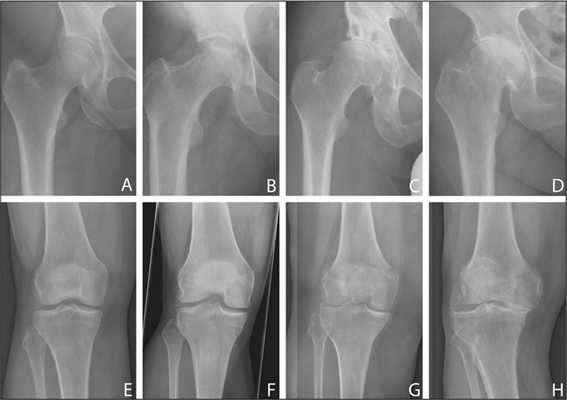

Степень артроза ТБС определяется характером и выраженностью симптомов. Наиболее часто клиническая картина соответствует определенной стадии патологии, которая устанавливается с помощью рентгенографии. Чем серьезнее повреждены хрящевые и костные структуры, тем интенсивнее боли и скованность движений.

Болезнь в динамике: от полного отсутствия до последней стадии.

С помощью рентгенограмм часто устанавливается не только степень тяжести деформирующего артроза, но и причины его развития. Увеличенный шеечно-диафизарный угол, скошенная и уплощенная вертлужная впадина свидетельствуют о дисплазии ТБС. А измененная форма проксимальной части кости бедра указывает на болезнь Пертеса, или юношеский эпифизиолиз. Ведущими рентгенографическими признаками непосредственно артроза являются остеофиты, сужение суставной щели, выраженное расширение бедренной головки.

Так выглядит больной сустав на рентгене (справа).